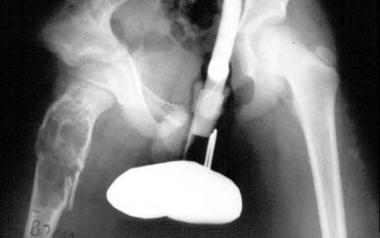

Large unicameral bone cyst of pelvis. Pathologic fracture is depicted. Note extension of cyst into region of proximal femoral physis.